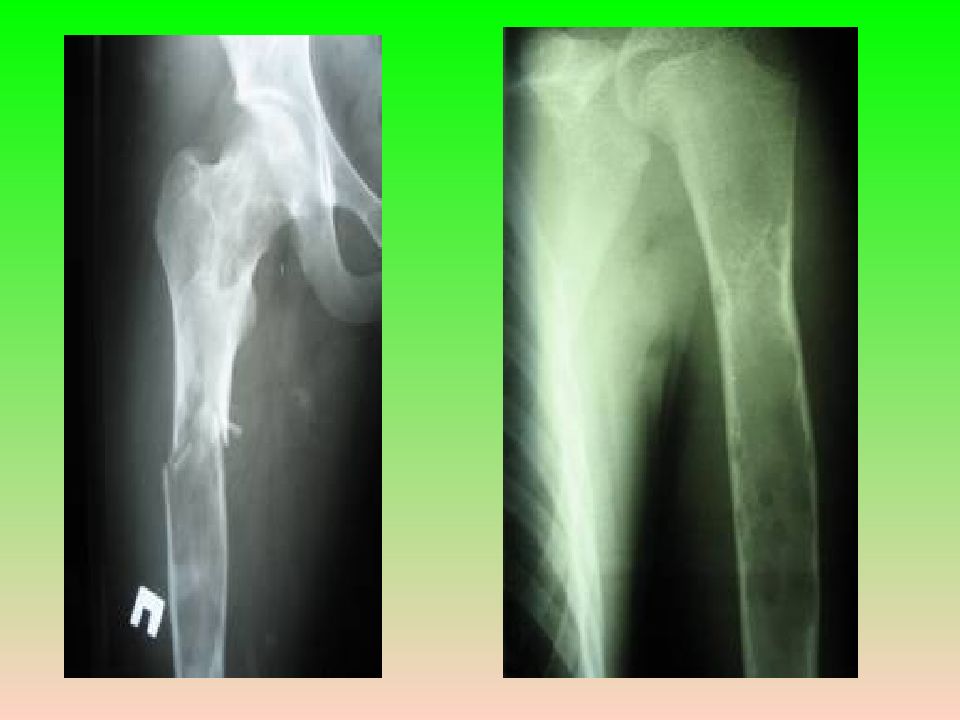

Слайд 8: Клиническая картина

Боли различной интенсивности, искривление и деформация костей, патологические переломы.  Рентгенологически — литическое поражение с чёткими контурами и склерозированными краями; может быть вздутие кости, патологический перелом. Клиническая картина

Встречается в любом возрасте, наиболее часто в первые десятилетия жизни (20% больных). Монооссальная форма несколько чаще встречается у лиц мужского пола, при полиоссальной форме соотношение лиц мужского и женского пола 2 : 1. Поражается любая кость, наиболее частая локализация: проксимальная часть бедренной кости, большеберцовая и плечевая кости, рёбра, кости черепа, шейного отдела позвоночника. Поражение костей позвоночника только в 2,5% случаев.